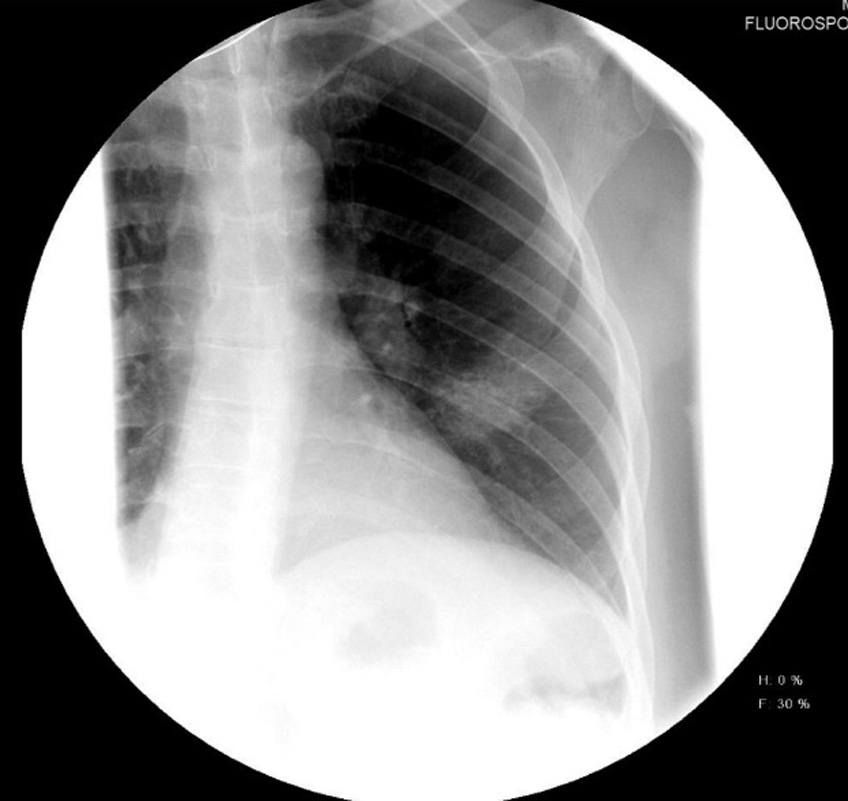

На обзорной рентгенограмме грудной клетки: левосторонняя пневмония основания легкого. На амбулаторном этапе лечения на фоне проводимой противовирусной терапии назначен дексаметазон внутримышечно (в/м) 2 р/день на протяжении 1 нед по схеме. В последующую неделю отмечалось ухудшение состояния, появился ночной профузный пот; повышение температуры до 39,3 °С и снижение сатурации кислорода (SpO2) до 87 %. Снижение температуры при приеме жаропонижающих средств отмечалось на несколько часов с дальнейшим значительным повышением. Отмечено нарастание симптомов интоксикации.

На обзорной рентгенограмме грудной клетки: усиление легочного рисунка, двусторонняя пневмония (в средних и нижних отделах легких).

На цифровых обзорных рентгенограммах органов грудной клетки в прямой проекции отмечается положительная динамика за счет уменьшения в объеме и интенсивности участков консолидации паренхимы по легочным полям с обеих сторон. При выписке из стационара в удовлетворительном состоянии: SpO2 94 %, температура тела 36,0 °С, одышка — только на фоне незначительной физической нагрузки, гипервентиляционный синдром, сильная астения, сухой непродуктивный кашель.

Рис. 1. Рентгенограмма органов грудной клетки до начала лечения препаратом бовгиалуронидаза азоксимер

Fig. 1. Chest X-ray imaging before treatment with Longidaza